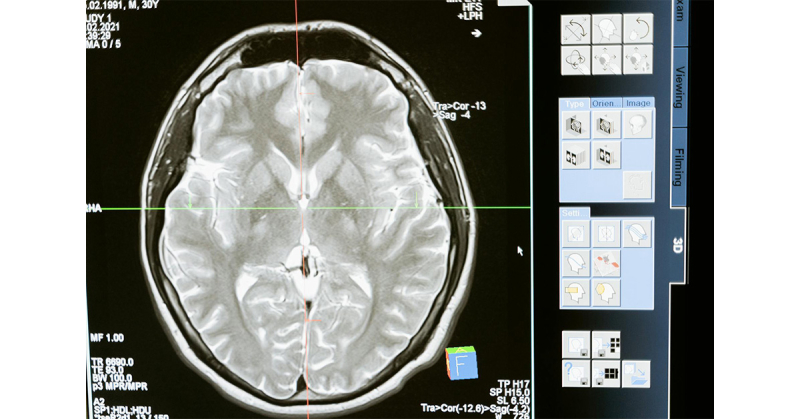

W dzisiejszych czasach nowoczesne technologie w diagnostyce znacząco ułatwiają wykrywanie różnych schorzeń neurologicznych. Badania takie jak:

- rezonans magnetyczny (MRI),

- elektroencefalografia (EEG),

- tomografia komputerowa (CT),

pozwalają na wczesne zidentyfikowanie problemów oraz monitorowanie postępów w leczeniu. Rozwój technologii w neurologii to duży krok w kierunku dokładniejszej diagnostyki i skuteczniejszego leczenia.